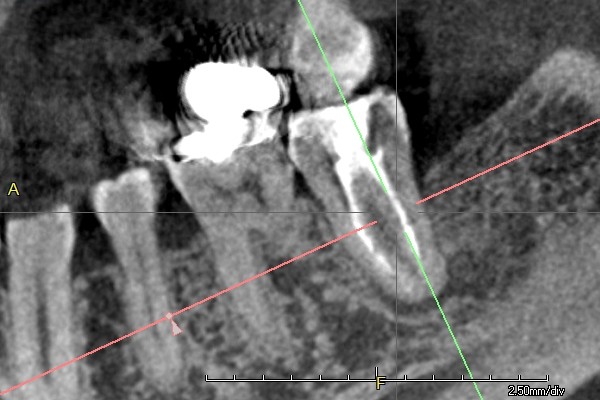

CTとは

3次元のX線写真(CT)を用いることで、従来の方法では捉えられなかった複雑な歯根の形態を明らかにし、より精密な治療計画を立てることが可能です。

この技術は、根管治療、親知らずの抜歯、インプラントや矯正治療の詳細な診断、さらには虫歯の深さの確認といった、多岐にわたる治療シーンで活用されています。

3次元CTの導入により、見えなかった部分を視覚化し、患者様へのより適切な治療提供を実現しています。

また、当医院のCTは根尖の病巣大きさを客観的に比較できます。

治療後の経過をみるCTは1~6ヶ月の期間を設け経過観察していくこともございます。